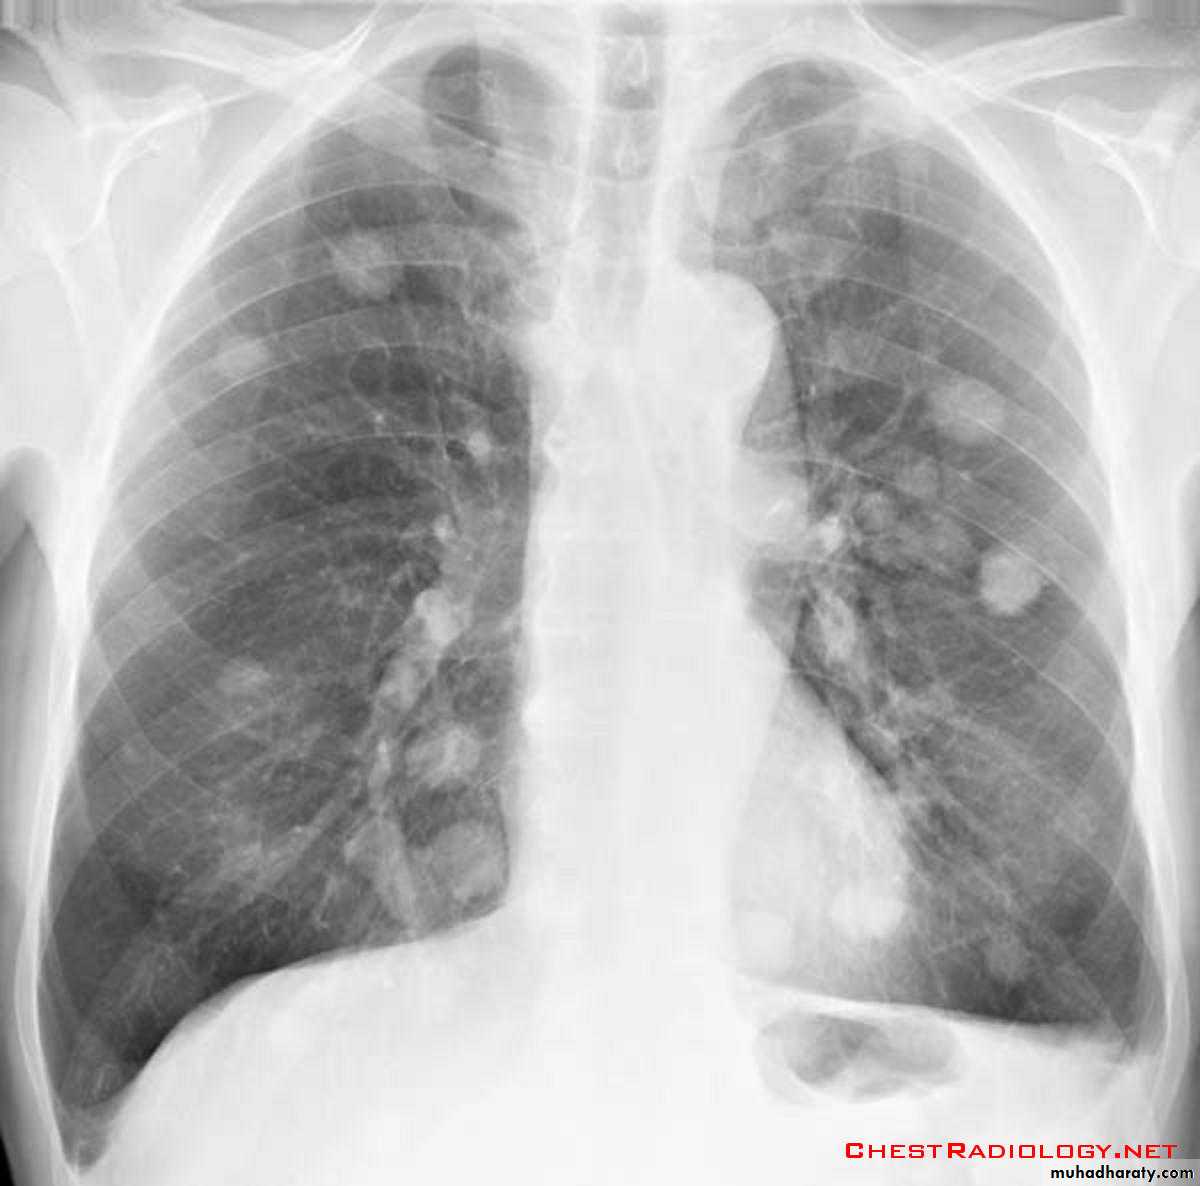

DDX of coin shadow

????????Answer

75. DDX of coin shadow

76. Coin lesion .